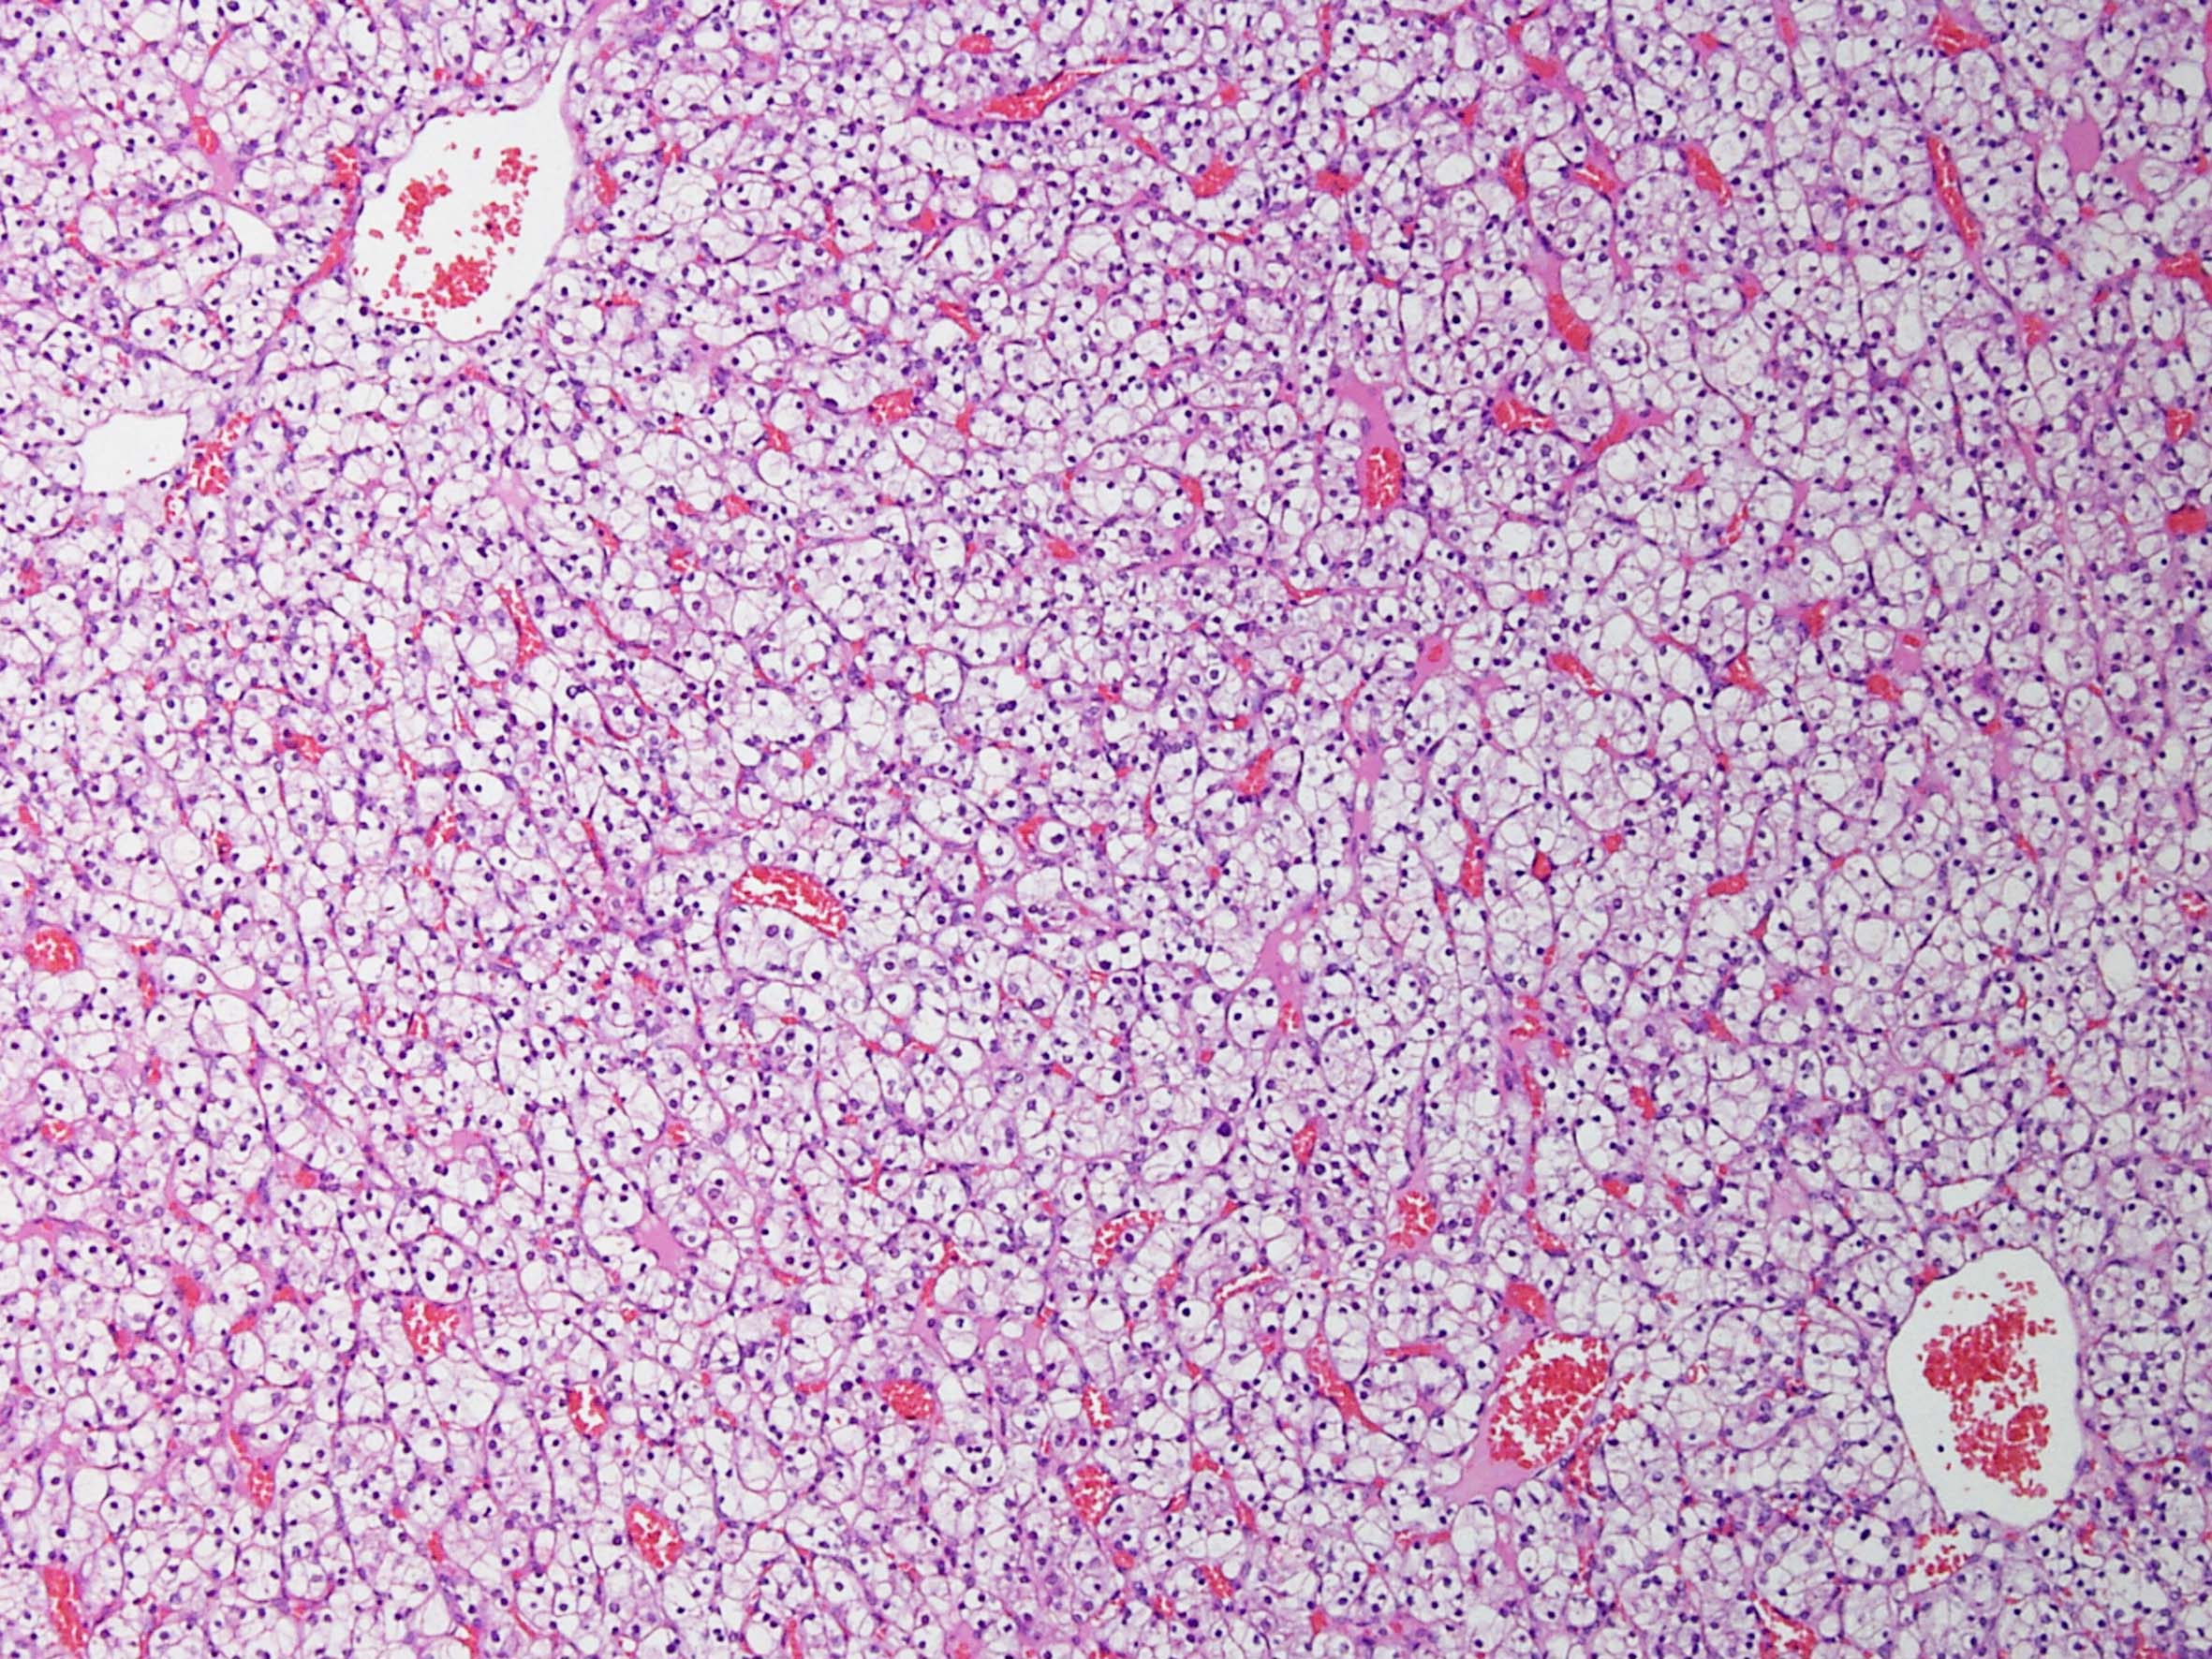

Classification of renal tumors

Case ID: 184